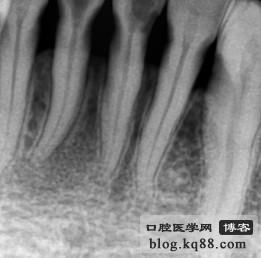

附一例簡單的宇森根管馬達(dá)病例:

來源于 網(wǎng)絡(luò)